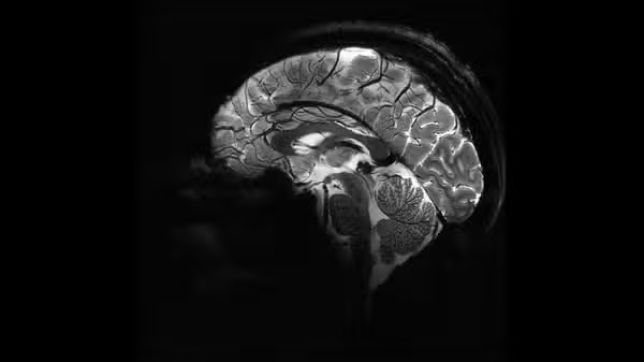

A autópsia revelou uma hemorragia subaracnóidea — um tipo de sangramento no espaço ao redor do cérebro. A análise identificou um aneurisma sacular rompido, com 11 milímetros de diâmetro, uma forma comum desse tipo de condição, também chamada de “aneurisma em baga”.

“Quando os aneurismas se rompem, eles liberam sangue que pode matar células cerebrais próximas e aumentar a pressão dentro do crânio. À medida que a pressão aumenta, o fluxo de oxigênio e sangue para o cérebro pode ser interrompido, o que pode levar à inconsciência e à morte”, explicaram os médicos no relatório, segundo a LiveScience.

Os especialistas sugerem que o esforço físico associado à excitação sexual pode ter causado um aumento temporário da pressão arterial, suficiente para romper o aneurisma, resultando na hemorragia fatal.

Mortes súbitas associadas à atividade sexual são incomuns. De acordo com estudos citados pela LiveScience, em cerca de 130 mil autópsias forenses, apenas 0,15% estavam relacionadas a relações íntimas, e a maioria das vítimas eram homens mais velhos com histórico cardíaco. Entre mulheres, esses casos são ainda mais raros e geralmente ligados a hemorragias cerebrais decorrentes do rompimento de aneurismas.